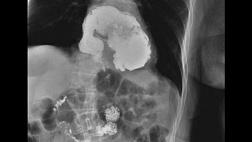

1. Туберкулез почек (нефротуберкулез) различают четыре стадии: туберкулез паренхимы почек, туберкулезный папиллит, кавернозный туберкулез почки, поликавернозный туберкулез почки.

1. Туберкулез почек (нефротуберкулез)

Туберкулез паренхимы почек

На эту форму приходится 80% УГТ. Почечная недостаточность есть, возможна пиурия. На урограммах или КТ с контрастным усилением строение чашечно-лоханочной системы обычное, деструкция и ретенция не определяются. При биопсии почек выявляется гранулематозный нефрит с казеозным некрозом. Может гломерулонефритом, или вторичным амилоидозом.

Туберкулезный папиллит. Развивается при вовлечении в процесс почечного сосочка. При развитии папиллярного некроза (казеификация гранулем) образуются полости (каверны).

Кавернозный туберкулез почки патогенетически развивается двумя путями – из туберкулеза паренхимы или из папиллита. В первом случае формируется субкортикальная каверна, не сообщающаяся с чашечно-лоханочной системой; во втором – каверна формируется за счет развития папиллярного некроза (казеификация гранулем).

Поликавернозный туберкулез почки предполагает наличие нескольких каверн, что ведет к резкому снижению функции органа. По мере развития процесса почка деформируется, кальцифицируется и становится нефункциональной. Осложнение – почечная недостаточность (риск развития плоскоклеточной карциномы).